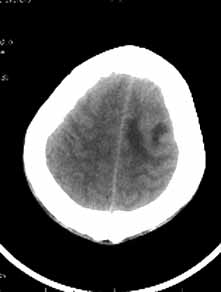

男性,36岁,头痛数年,近期伴有视蒙。

ct诊断:左额颞部脑膜瘤。